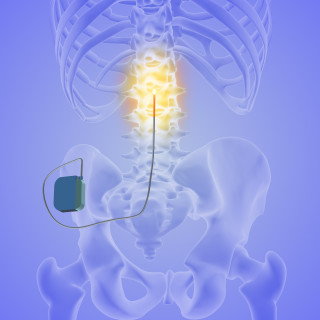

Rolf Hanoa Nevrokirurgisk avdeling Rikshospitalet og Ullevål sykehus 1951 - 2021 Norsk helsepolitikk for nevrokirurgiske pasienter. 416 s., tab., ill. Bergen: Fagbokforlaget, 2023. Pris NOK 549 ISBN 978-82-450-4320-4 Boken tar med leseren på en interessant reise, fra pionertiden til moderne tid, i nevrokirurgi ved Rikshospitalet og Ullevål sykehus. Vi får innblikk i en enorm fagutvikling, historiske milepæler, noen nedturer samt en lang rekke omorganiseringsprosesser. Boken er mer enn et festskrift til de to viktige norske sykehusavdelingene, men berører også omstridte behandlingsmetoder...